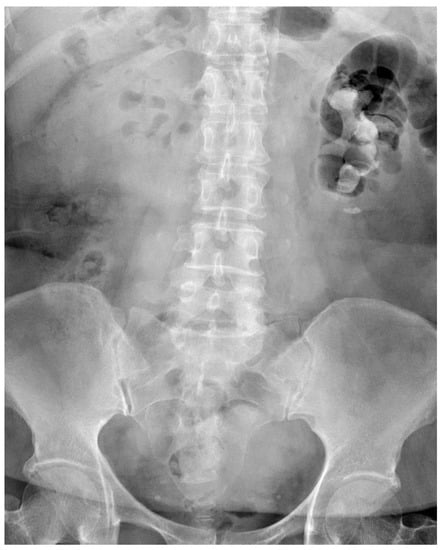

Percutaneous Nephrolithotomy Combined Antegrade Flexible Ureteroscope for Complete Staghorn Stones: A Case Report of a New Concept of Stone Surgery

2. Case Presentation